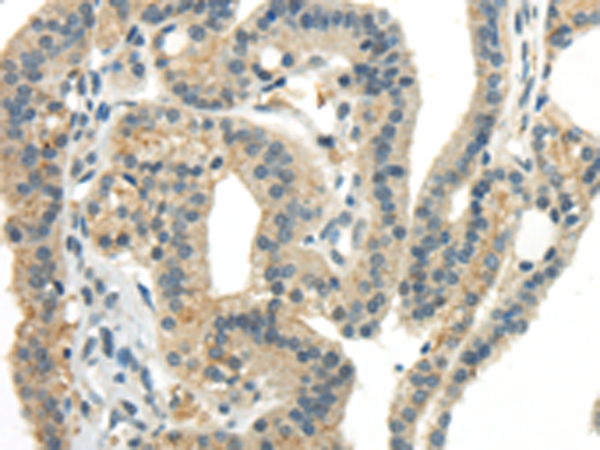

分类: 科研抗体货号: P10717别名: ATG6; VPS30; beclin1应用: WB,IHC反应种属: Human, Mouse, Rat